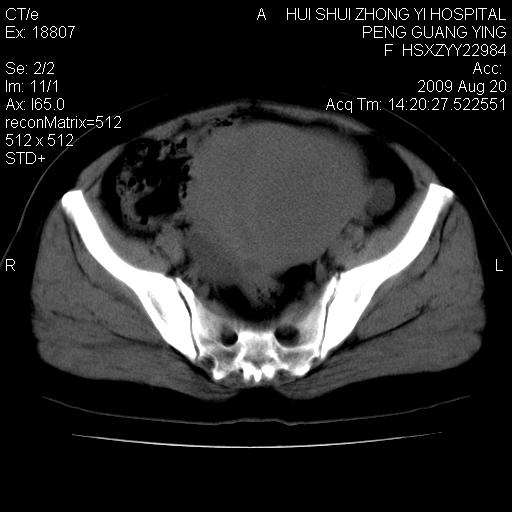

标题: CT21707:女,42岁,因发现下腹部包块2月。 [打印本页]

标题: CT21707:女,42岁,因发现下腹部包块2月。

病灶来源——子宫?附件?

从平扫角度看本人还是倾向于子宫肌瘤诊断,宫腔少量积液。

目前的影像表现显示肿块位于腹腔及盆腔,但具体定位,分清来源较困难,是否来源于卵巢、子宫无法定论,子宫直肠及子宫膀胱周围脂肪间隙尚较清晰,如果患者有过腹腔好或者盆腔手术史,也可以形成不典型的血中,最好手术后定为定性,我期待结果。

软组织密度,与子宫一致。双侧卵巢形态、密度好,不支持来源于卵巢。